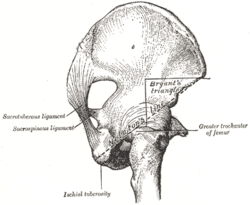

Nélaton’s line and Bryant’s triangle.